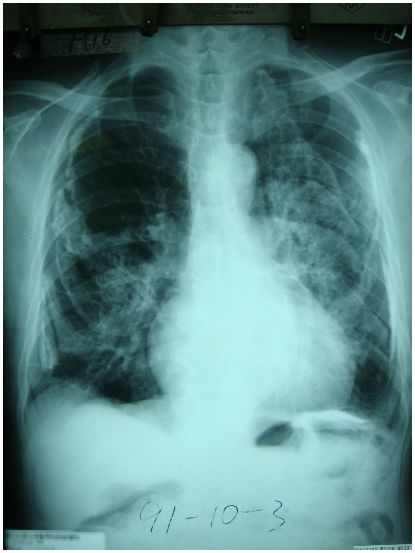

4. 75歲男性,未曾吸菸,主訴長期呼吸困難,胸部X光如圖所示,下列有關其診療之敘述,何者正確? (A) 可能會呈現慢性換氣不足(hypoventilation) (B) 血中HCO3- 濃度可能會降低 (C) 吸入 anticholinergic 是首選治療藥 (D) 胸部X光顯示是矽肺症 (Silicosis) (E) 肺功能FEV1 / FVC 通常低於0.6